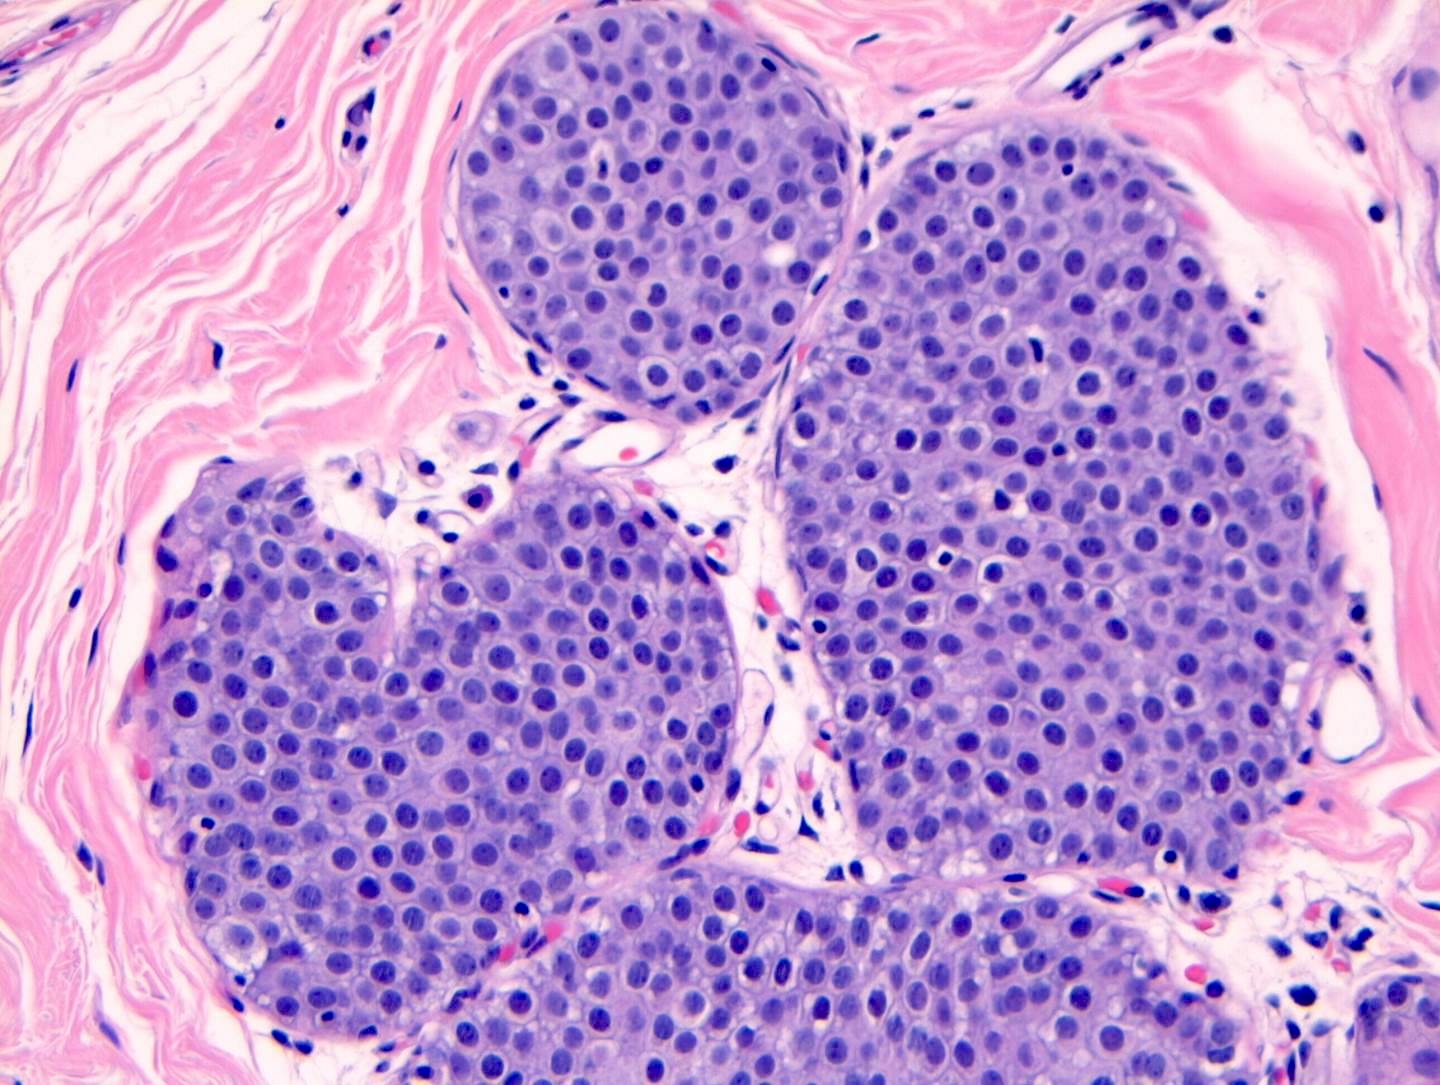

Microscopic (histologic) description

- LCIS involves the terminal duct lobular unit (TDLU), filling and distending acini

- > 50% of the acini in a TDLU must be filled and expanded to qualify as LCIS; otherwise, called atypical lobular neoplasia

- Lobular distention is defined as the presence of ≥ 8 cells in the cross sectional diameter of an acinus

- Involved lobules may be compared with uninvolved lobules to estimate the degree of distension

- Classic LCIS cells are monomorphic, evenly spaced, loosely cohesive and do not show polarization or gland formation

- 2 types of cells are described:

- Type A: nuclei are small to slightly enlarged (1 - 1.5x size of lymphocyte) with uniform round nuclei and inconspicuous nucleoli

- Type B: nuclei larger (2x size of lymphocyte), more abundant cytoplasm and more prominent nucleoli

- Type A and B cells can coexist in the same lesion

- Cytoplasm of LCIS cells is typically pale to lightly eosinophilic with indistinct cell borders

- In almost all cases of LCIS, at least some cells contain intracytoplasmic vacuoles or lumina, which may contain an eosinophilic globule; this feature is not specific to LCIS

- Outer layer of myoepithelial cells is retained in the acini and ducts involved but it may be attenuated

- Classic LCIS does not show significant nuclear pleomorphism or mitosis

Microscopic (histologic) images

Contributed by Anna Biernacka, M.D., Ph.D.